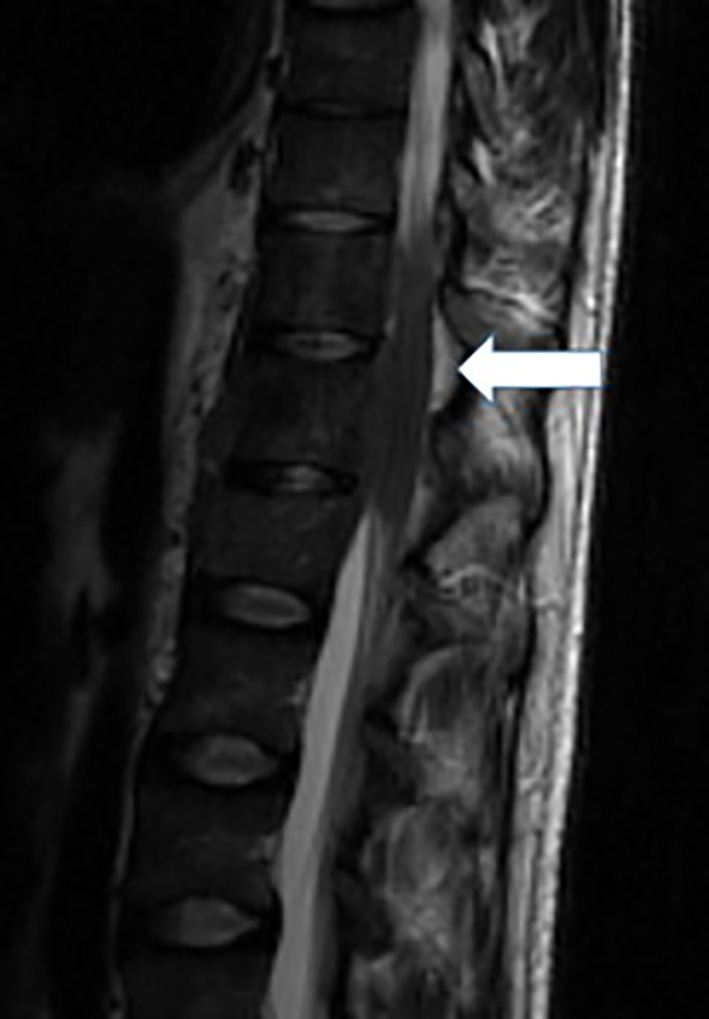

Magnetic resonance imaging (MRI) of the spine reported an epidural mass at T12-L1 level with spinal canal stenosis at T12 level (Fig. 1). Further workup included CT of chest/abdomen and pelvis which showed a large anterior mediastinal mass measuring 8.4 × 5.9 cm (Fig. 2), mixed lytic/sclerotic bony lesions in the spinal bodies from T10 to L1 (Fig. 3), the iliac crests, left sacrum, and the left ischial tuberosity and left supraclavicular lymphadenopathy (Fig. 4). The differential at that time inclined towards germ cell tumor and lymphoma and decision was made to biopsy the left supraclavicular fossa lymph node.

Figure 3. Image depicting mixed sclerotic as well as lytic lesions in the spine.